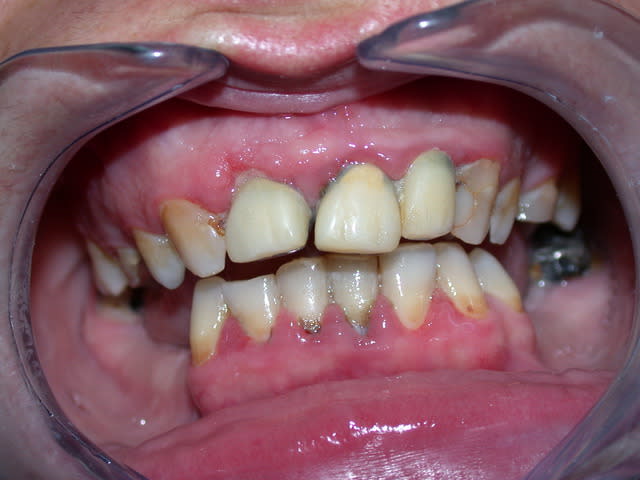

JH, 40 ans,

motif de consult: sa femme ne veux plus l'embrasser ...